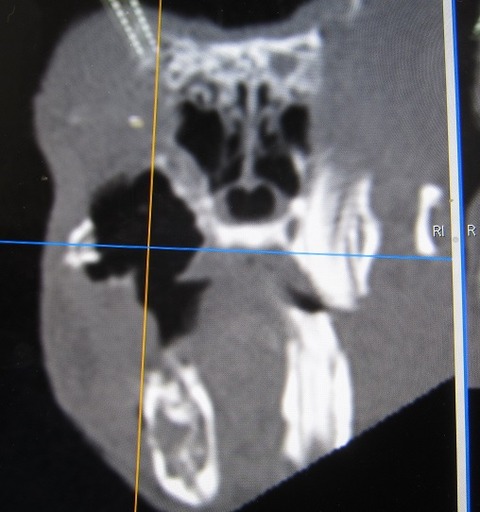

途中経過をCTで

まだまだたくさん残ってますが、👆これが👇こうなります。

完全に取り切れてない部分もありますが、すでに時間もかなりかかっていたのでひとまず終了。